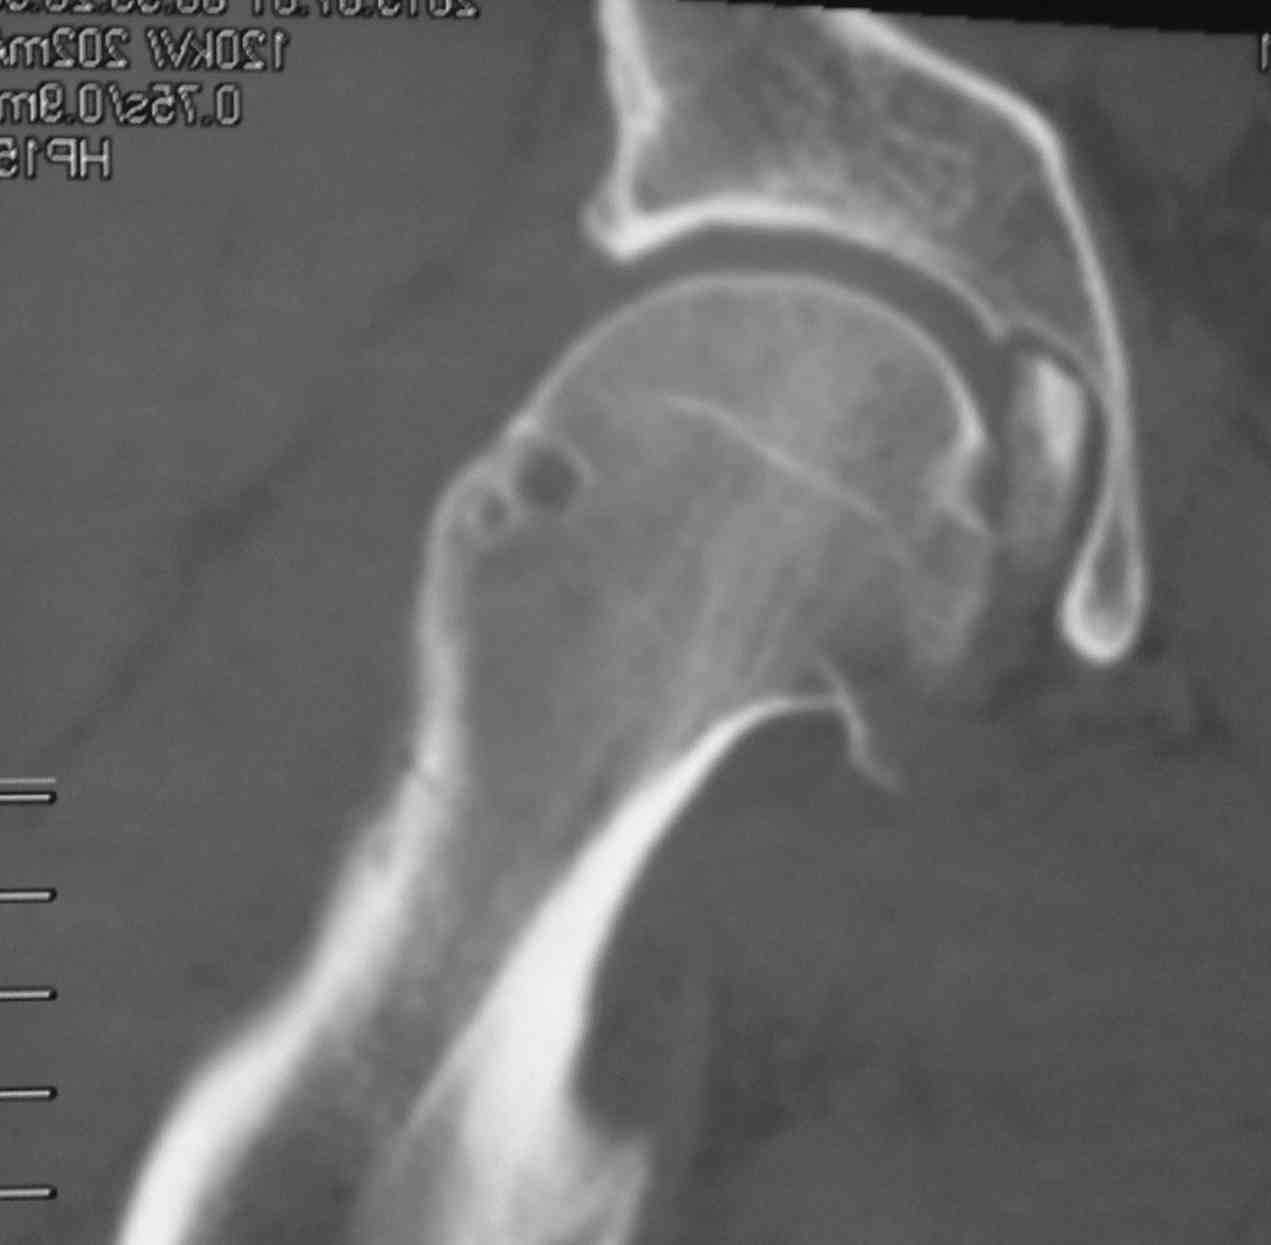

Фрагмент в полости тазобедренного сустава большой. Мы бы оперировали. В похожем случае, но уже у нас, (см. приложение) внутрисуставной осколок был значительно больше предполагаемого.

Никита, фрагмент в вашем случае несколко в иной локализации и он реально "пережует" впадину, здесь он в ямке.

Добрый день, коллеги! Повреждение вертлужной впадины вероятнее всего 62-А1.2 чистый переломовывих, оскольчатый перелом задней стенки, при этом внутрисуставной фрагмент, является частью артикулирующей поверхности ацетабулюм, а следовательно его необходимо извлечь и поместить на место, иначе мозаика может не собраться. Про FAI временно можно не вспоминать (не до него), поскольку наиболее тяжелое повреждение голени требует адекватного вмешательства.На представленных рентгенограммах таза после операции все отлично, полную картину даст КТ.